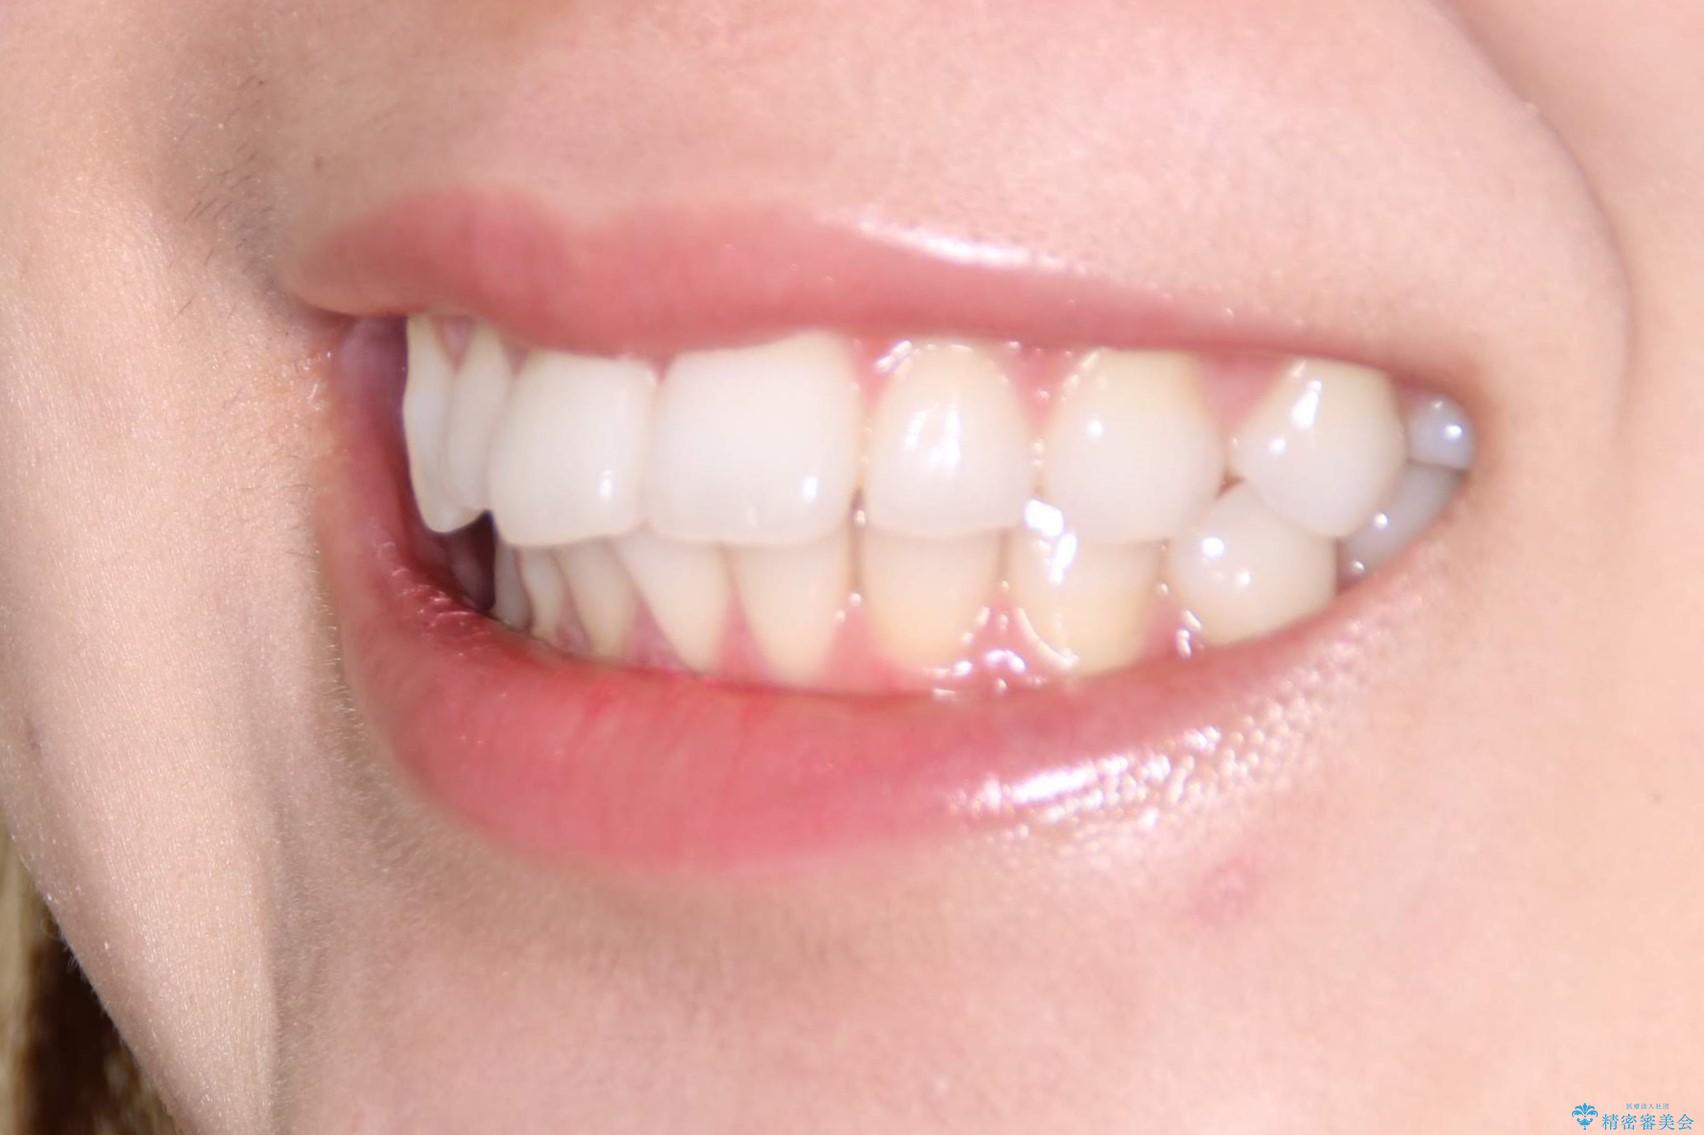

インビザラインで出っ歯を改善する 抜歯をしないinvisalign治療

- 20代女性

- 1年5ヶ月

- 非抜歯・遠心移動による前突の改善をマウスピースにて計画した。

非抜歯矯正の場合、大きく前歯を下げることはできませんが、奥歯の遠心移動や歯のサイズダウンにより歯軸を立て、見かけ上の出っ歯感をある程度改善することができます。